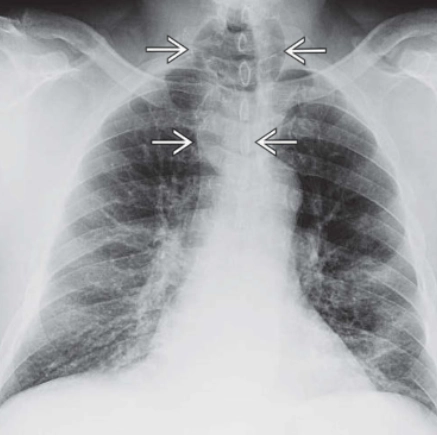

Khí quản hình vỏ kiếm (Sabre-sheath trachea)